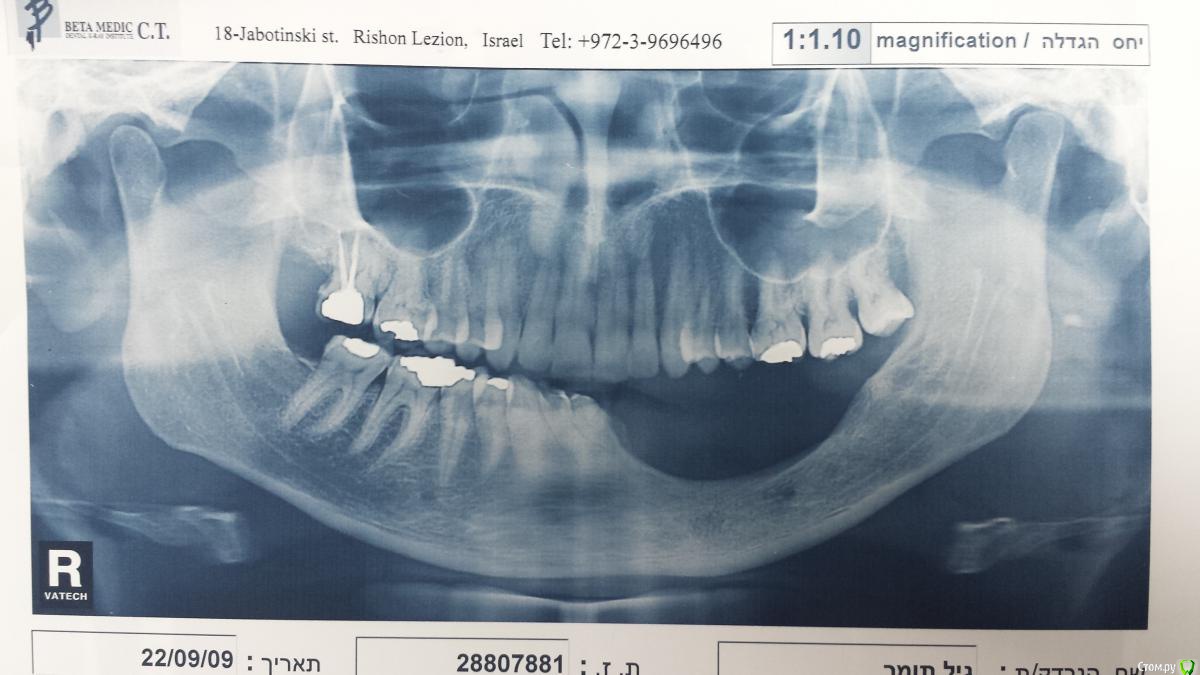

natan. Опубликовано 21 мая, 2015 Поделиться Опубликовано 21 мая, 2015 пациент после удаления амелобластомы. Был выполнен DO 4 Ссылка на комментарий

natan. Опубликовано 22 мая, 2015 Автор Поделиться Опубликовано 22 мая, 2015 Здравствуйте Ilgamsa, как вас по имени называть? Из за того что span (промежуток) кости огромный 31 - 37 было решено выбрать 2 дистрактора так как 2 отдельных и поменьше легче контролировать чем один длинный где ты теряешь '' силу '' по краям. Обратите внимание на '' манипуляцию''выполненную чтобы не повредить mental nerve (видно на рентген снимке с дистрактором). Активация двух сегментов кости была одновременной.в конце между двумя сегментами была добавлен bioss. Поищу снимки 2 Ссылка на комментарий